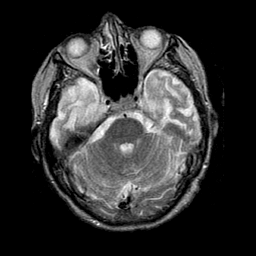

Pick's Disease, MR Study mr-t2 -- Slice #6

[Home][Help][Clinical] Slice 6